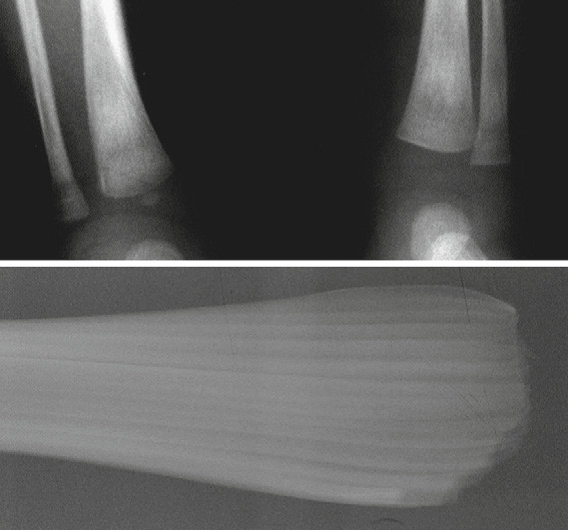

NAT - metaphyseal corner fracture

NAT - metaphyseal bucket handle fracture

Fractures specific for NAT

• posterior rib fractures

• secondary to an adult squeezing an infant’s thorax

• close to costovertebral joints

• may be sutble prior to callus formation

• metaphyseal corner fracture

• extends through primary spongiosa of the metaphysis - the weakest portion

• secondary to forceful pulling of an extremity

• broken metaphyseal rim appears as a corner fracture triangular piece of bone when seen tangentially; or as a bucket-handle fracture when seen obliquely